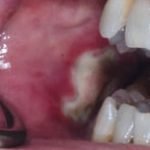

Fig. 10B Caso clinico di aumento di volume gengivale indotto dalla assunzione di amlodipina (calcio-antagonista).